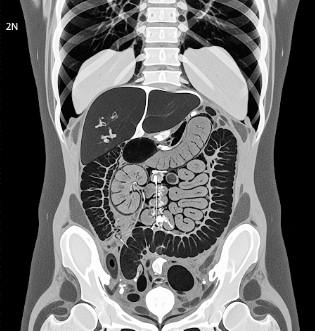

A CT scan (computed tomography scan) is a medical imaging technique that uses X-rays and computer processing to create detailed cross-sectional images of the body. CT scans provide clear visualization of bones, organs, blood vessels, and soft tissues, enabling precise diagnosis of various medical conditions.

CT scans are fast, painless, and non-invasive, though the procedure varies slightly depending on the body area being imaged.

- Image reconstruction: Computer processes the data into cross-sectional images; 3D images may be generated.